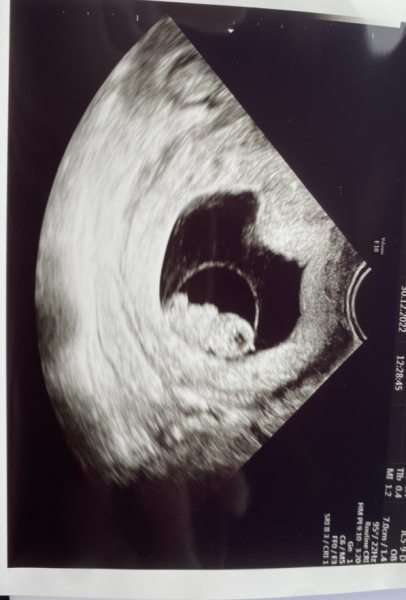

My scan went well today so thought I’d give you ladies an update. We saw a little heartbeat and arms and legs starting to grow. Measuring exactly as I thought due to ovulating later than normal - I’m 8weeks 5 days. Only 1 day out based on my own calculations. I had to have an internal scan due to having a tilted uterus - they could see a heartbeat but not a clear image. My heart was racing whilst I was waiting for them to see the baby but in the end the internal one was worth it. ❤️